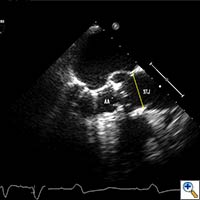

Echocardiography is important to confirm the severity of aortic stenosis, rule out bicuspid aortic valve (which a relative contra-indication) and to size the aortic annulus and left ventricular outflow tract (LVOT) (Figure 1). It is also necessary to assess for concomitant Mitral valve disease. Mild to moderate mitral regurgitation (MR) is frequently associated with AS in elderly patients but does not usually require any surgical intervention and does not represent a contraindication for TAVI. However, severe MR with bulky mitral annular calcification involving the LVOT has been associated with worse midterm outcome and increased risk of para-valvular leak (2).

Figure 3. Direct echocardiographic visualization of the left ventricular outflow tract during valve insertion.